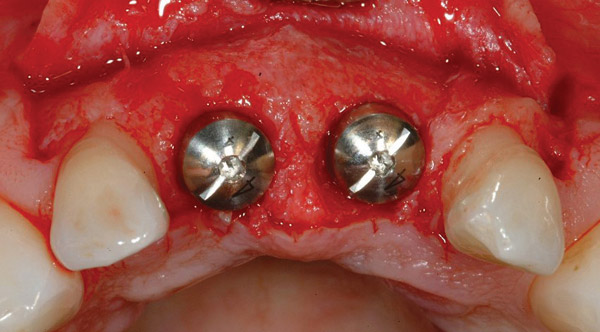

Figure 2  The orientation of the healing abutments after the patient had undergone extraction, guided bone regeneration, and implant placement. Note the wide spacing between the central incisor implants.

Figure 2